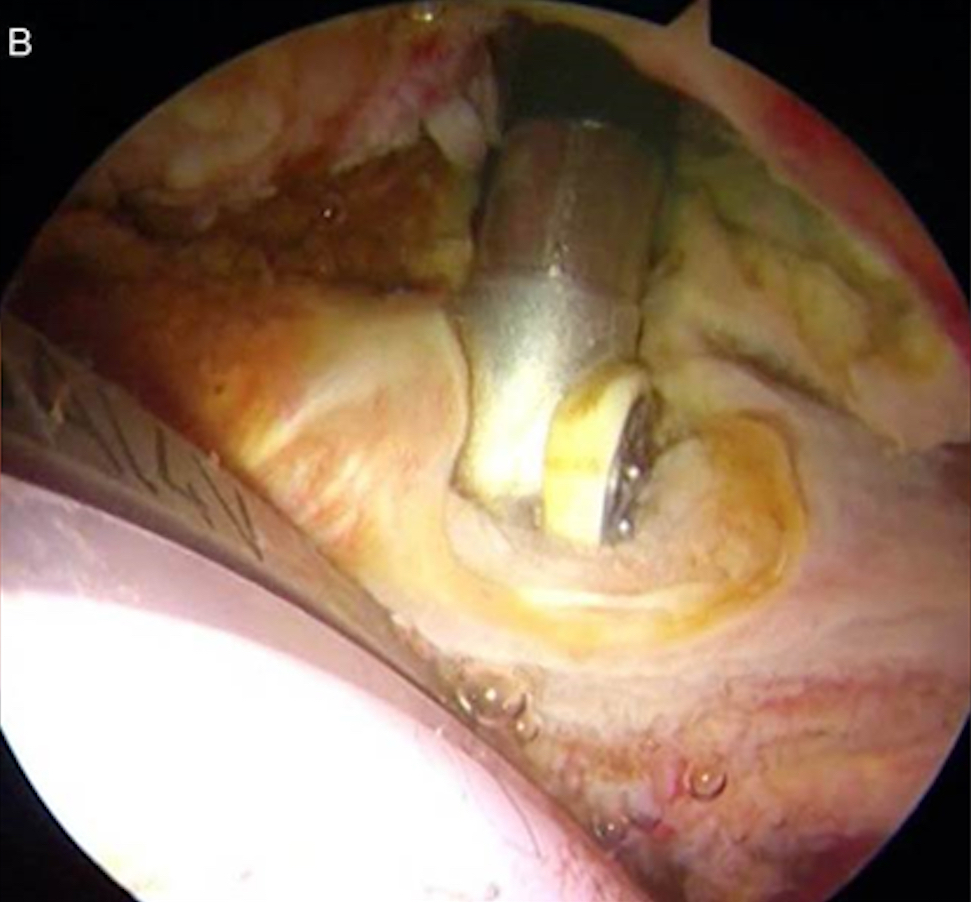

Cosa curiamo con l’atroscopia d'anca - Il conflitto del tendine Psoas con la Coppa Acetabolare nelle protesi d’anca dolorose

Questa è una patologia che colpisce alcuni pazienti (circa 0,5% - 3%) portatori di protesi totale d’anca, quando la coppa acetabolare viene posizionata con sporgenza eccessiva anteriore. Questa sporgenza comporta lo sfregamento del tendine Psoas (muscolo flessore dell’anca) sulla protesi, creando dolore nel flettere attivamente la coscia (dolore nell’entrare in auto, nel salire le scale, nel portare la gamba sul letto), costringendo il paziente ad accompagnare l’arto con le mani.

Il trattamento artroscopico consiste nell’eseguire il Release del tendine (senza toccare la protesi) apportando immediato sollievo al paziente (Fig.5a e 5b).